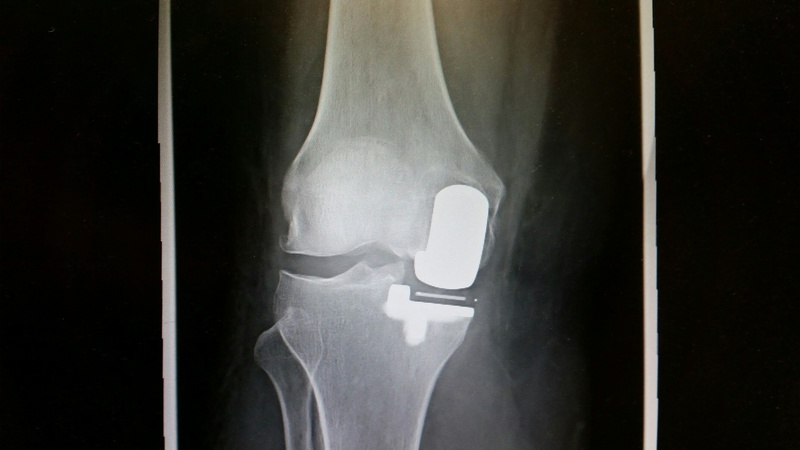

Knie-Totalprothese

Wenn bei fortgeschrittener Arthrose Schmerz und Funktionseinschränkung die Lebensqualität erheblich mindern und durch Medikamente nicht in den Griff zu bekommen sind, ist der Ersatz durch ein künstliches Gelenk (Endoprothese) zu empfehlen. Bei dieser Operation werden die zerstörte Gelenkknorpeloberfläche, die Meniskusstrukturen und das vordere Kreuzband entfernt. Abhängig vom Ausmaß der Zerstörung am Kniegelenk erfolgt die Auswahl der richtigen Knieprothese. Wir unterscheiden zwischen unicondyären („Schlittenprothese“) und bicondylären Oberflächenersatzprothesen bei ausgedehnterer Arthrose. Die Prothese kann dabei zementfrei oder mit Knochenzement im Knochen verankert werden. In seltenen Fällen ist auch der Einsatz von Revisionsknieprothesen erforderlich. Das ist unter anderem von der Qualität des Kapsel-Band- Apparates und des Knochens abhängig.

Die Arthrose eines Kniegelenkes kann durch Röntgenuntersuchungen gesichert und der Schweregrad beurteilt werden. Das Ausmaß einer Achsfehlstellung wird mit einer Ganzbein-Aufnahme überprüft. Manchmal kann es erforderlich sein, weitere Untersuchungen wie eine Kernspintomographie zur Sicherung der Diagnose durchzuführen.